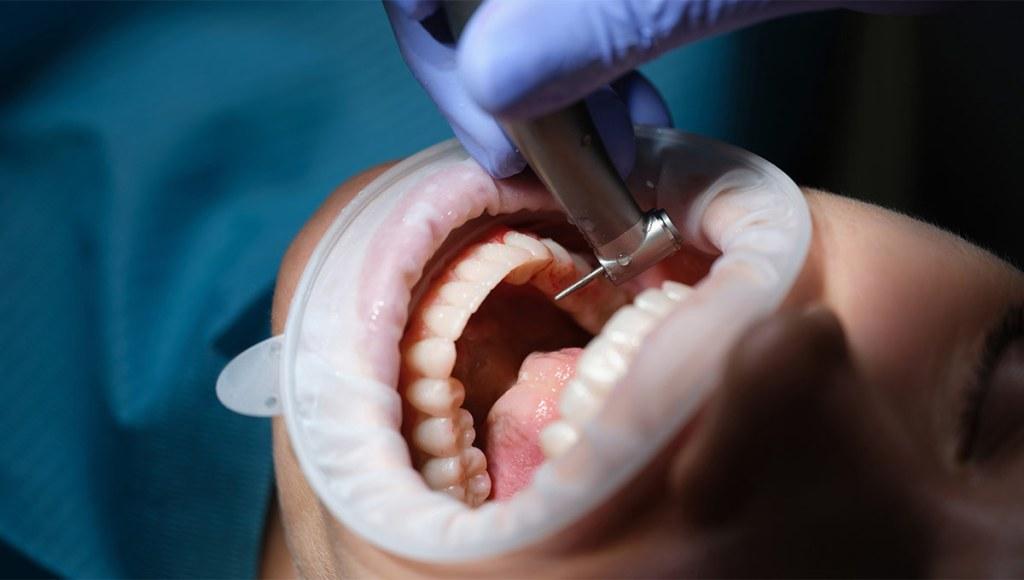

Our practice is built around the full arch restoration, including All-on-4, All-on-6, and zygomatic implant procedures. These treatments replace an entire arch of missing or failing teeth with a fixed, permanent set of new teeth supported by as few as four dental implants. Many of our patients receive temporary teeth on the same day as their surgery, leaving our office with a complete smile.

Every new patient receives a complimentary consultation that includes a 3D cone beam CT scan. This imaging technology creates a detailed three-dimensional map of your jaw, allowing our surgeons to evaluate bone density, identify nerve locations, and plan implant placement with sub-millimeter accuracy before any surgery takes place.

Our in-house dental laboratory is central to what makes Fusion different. While most implant providers send lab work to external facilities, adding weeks to treatment timelines, our on-site lab crafts custom prosthetics under the same roof. This means same-day temporary teeth for full arch patients, faster adjustments, and tighter quality control over every restoration we deliver.